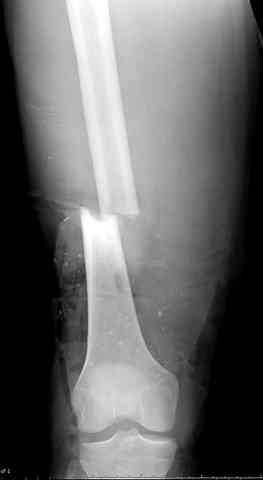

После пары Irrigation& Debridment с вакуумом можно провести окончательную фиксацию интрамедуллярным методом. Чем быстрее, тем лучше, потому что сроки нахождения наружных фиксаторов на конечности тоже имеют значение, риск осложнения увеличивается после длительного пребывания наружного фиксатора.

Открытые переломы, если имеется хороший доступ из раны можно сопоставить и зафиксировать первично пластиной, потому что несопоставленные переломы намного труднее репонируется в поздние сроки. Активизация больного за счет стабилизации кости благоприятно влияет на сращение, а также облегчается манипуляция по закрытию дефекта.

здесь случай с политравмой, перелом зафиксирован наружным фиксатором, после третьей irrigation&debridment фиксация бедра пластиной с последующей кожной пластикой.